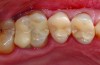

A clinical example of a resin-bonded silica-based ceramic (porcelain laminate veneers) restoration is depicted in Figure 1 and Figure 2.

Fig 2. Postoperative intraoral view after restoration of all maxillary incisors with minimally invasive adhesively bonded porcelain laminate veneers. Clinics by Dr. Markus B. Blatz; dental technology by Cusp Dental Laboratory, Boston, MA.